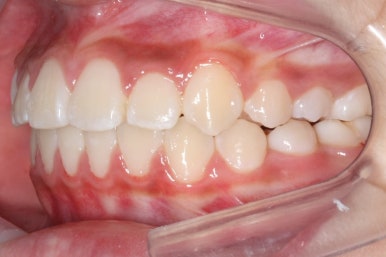

초진 시의 모습입니다.

해당 환자분은 영구치가 아직 모두 나오지 않았지만 서둘려 교정을 시작한 이유는 2급 부정교합에 약간 가까웠기 때문입니다.

2급 부정교합은 아래턱이 작아 위치가 뒤에 있다거나 위턱이 반대로 커서 앞에 있는 경우로 상대적으로 입이 튀어나와 보이게 하며 아래턱은 무턱처럼 보이게 합니다.

골격분석과 X-ray 등으로 확인했을 때, 이번 환자분은 위턱이 약간 상대적으로 나와있다고 판단이 되었습니다. 위쪽 치열은 아래쪽 보다 앞으로 나와있으며 특히 어금니가 앞쪽으로 나와있었어요.

연산동덧니교정을 하고자 키다리아저씨치과에 처음 내원했을 때와 개선이 된 후의 비교 모습입니다. 영구치가 모두 나왔고 덧니가 개선이 된 후에 마무리가 되었습니다.